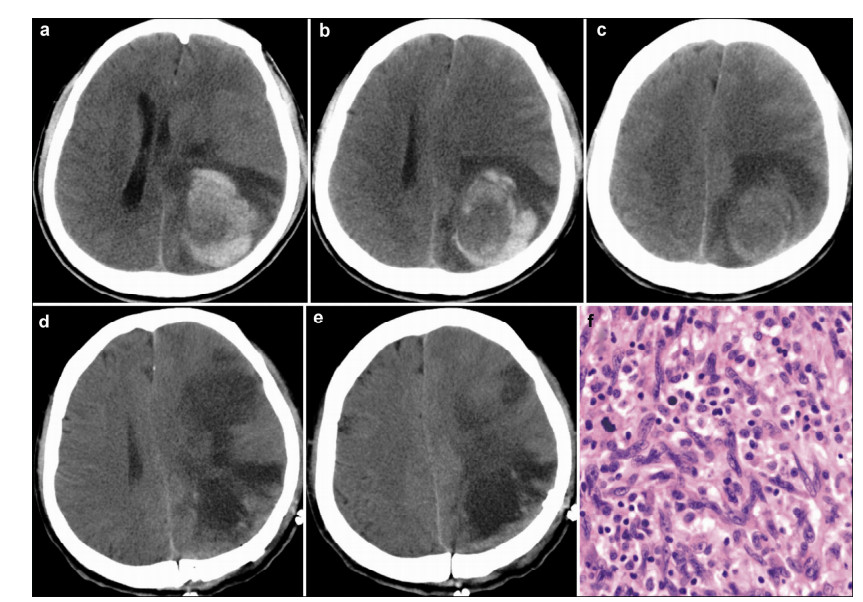

A 44-year-old previously healthy man presented with headache and vomiting for 8 days. He did not have any head trauma history. Neurological examination revealed no positive signs. Cranial CT scan showed a hematoma in the left occipital parietal lobe (Figures 2a-2f). The density of the hematoma was hetero-geneous on the CT image. A glioma apoplexy was suspected. Immediate surgery with a left parietal approach was performed to clear the hematoma and resect the tumor. The tumor was totally resected. The pathological diagnosis was MFH. The patient recovered well after surgery and received postoperative radio-therapy and chemotherapy. However, 4 months after surgery, he died from the recurrent tumor.

| Figure 2 Case 1. Preoperative cranial CT shows an evident hematoma in the left occipital parietal lobe (a–c) . Postoperative cranial CT shows total resection of the tumor (d & e) . Pathological examination (f) reveals the diagnosis of MFH. (Hematoxylin & eosin staining, ×100) |